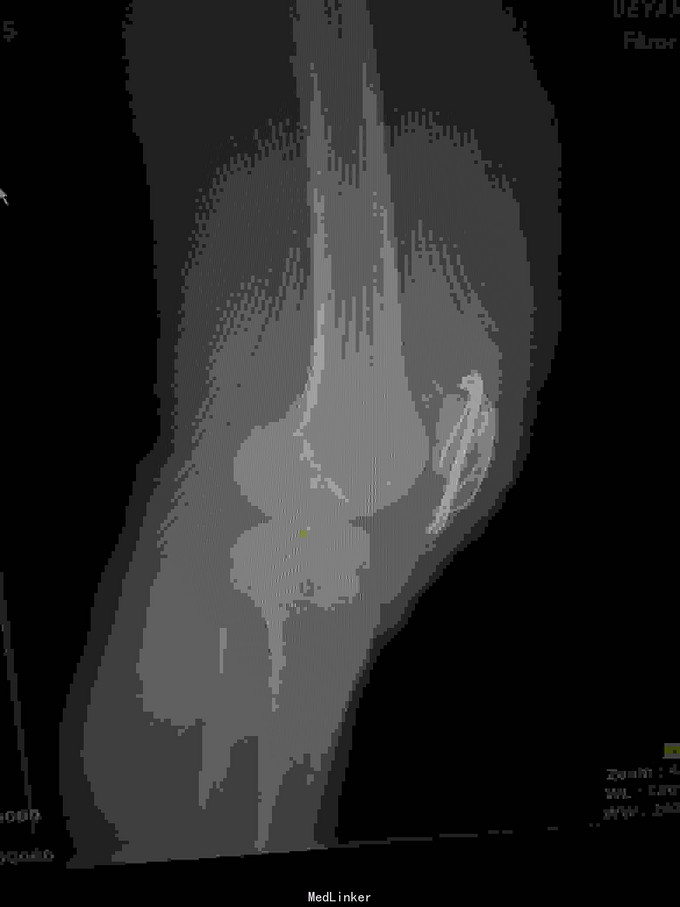

左髌骨粉碎性骨折

骨折 髌骨骨折

查体:左下肢活动受限,背伸障碍,左膝关节明显肿胀,压痛,扪及骨擦感,左足感觉及血循环可。 x片:左髌骨骨折。

诊断:左髌骨粉碎性骨折; 治疗,石膏固定,消肿止痛,行髌骨骨折切开复位克氏针内固定术,术中克氏针张力带钢丝固定,术后石膏固定。